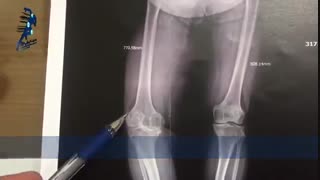

آرتروز زانو (knee osteoarthritis) یکی از بیماری های شایع بین مردم است که به دردهای شدید در ناحیه زانو منجر می گردد ( knee pain ) و باید درمان گردد. در صورت بی توجهی به آرتروز، این مشکل حادتر شده و به تعویض مفصل و جراحی منجر خواهد شد. روش های دارویی دارای عوارض سنگین بوده و درمان مناسبی نیستند. اما استفاده از حرکات ورزشی برای درمان آرتروز زانو بسیار موثر و کار آمد بوده و هیچ گونه عوارضی ندارد (knee osteoarthritis exercises).